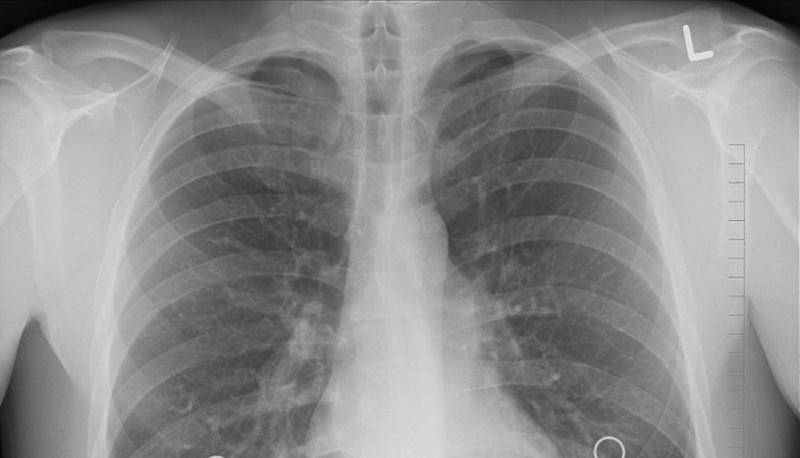

Рентген

Рентгеновские исследования являются самым распространенным и доступным методом диагностической визуализации. Его обычно используют для диагностики заболеваний костей, переломов, вывихов, воспалений и новообразований.

Во время рентгена исследуемая часть тела помещается между рентгеновским аппаратом и фотопленкой. Затем аппарат посылает излучение через тело, отражая его внутреннюю структуру на пленке. Кости и другие плотные объекты поглощают излучение и выглядят белыми на снимке. Мягкие ткани на рентгеновских снимках выглядят более темными и даже черными.

Хотя количество излучения, используемое для рентгеновского снимка, не считается опасным, у данного метода могут быть противопоказания, например, беременность. Беременным женщинам следует проводить рентгенографию только в случае, если польза от диагностики превышает потенциальный риск для плода.

Наиболее старый и привычный метод визуализации человеческого тела. Применяют рентген повсеместно, от хирургии до стоматологии. Метод прост и понятен: человека облучают особыми лучами, которые легко проходят сквозь мягкие ткани и задерживаются в твёрдых. Благодаря этому принципу, на фотоплёнку или датчик, расположенные на противоположной от источника лучей стороне, передаётся изображение, а в распоряжение врача попадает рентгенография или рентгеноскопия.

Главные плюсы такого обследования: быстрота и стоимость. Рентгеновскими аппаратами оснащены практически все больницы, процедура проходит быстро и стоит недорого.

Главные минусы: облучение и качество изображения. При проведении рентгенографии пациент облучается, а картинка получается двумерной. Врач с трудом может разглядеть внутренние органы по отдельности, поскольку их тени перекрывают друг друга. Также невозможно детально разглядеть хрящевую ткань и мозг. Хрящи практически не задерживает лучи, мозг надёжно закрыт черепной коробкой. Для их исследования рентгенография не подойдёт.

Наиболее эффективно будет проводить рентгенографию при повреждениях костей, суставов и зубов.

Пресловутый COVID во многих случаях первично диагностируется уже на обычных рентгеновских снимках. То же с другими проблемами легких.

Даже на рентгеновских плоских снимках видно COVID

Аналогично, первичная диагностика ряда заболеваний и состояний человека, не требующих срочного вмешательства, диагностируются более простыми и дешёвыми методами.